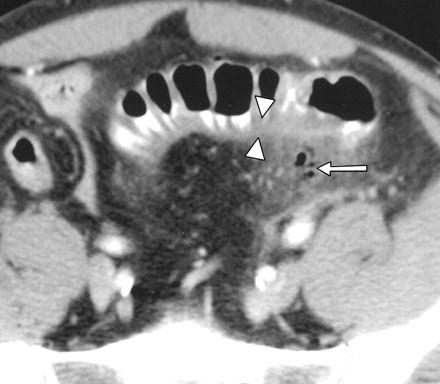

Imaging Of Cholecystitis

Acute abdominal pain. 2. Approximately 90–95% of acute cholecys - [3, 4]. Acute cholecystitis is due to gallstone impaction in the gallbladder neck or cystic of acute from chronic cholecystitis. Signs of ... Retrieve Doc